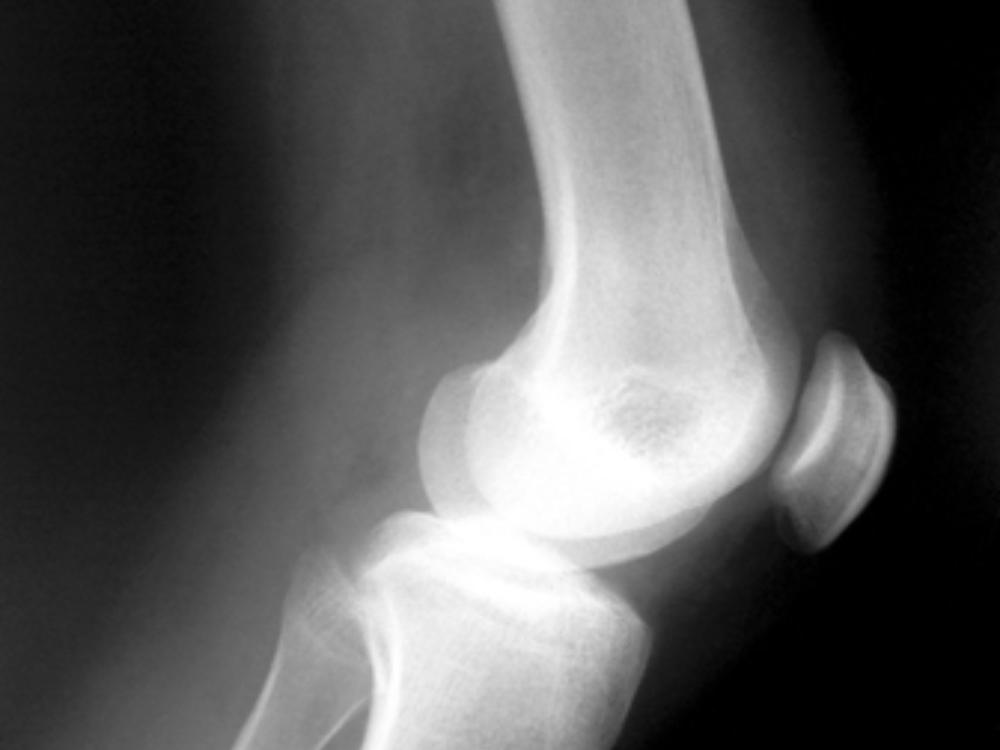

Перед курсом лечения пациент в обязательном порядке должен получить верный диагноз на основании рентгеновских снимков, показаний УЗИ и, зачастую, МРТ.